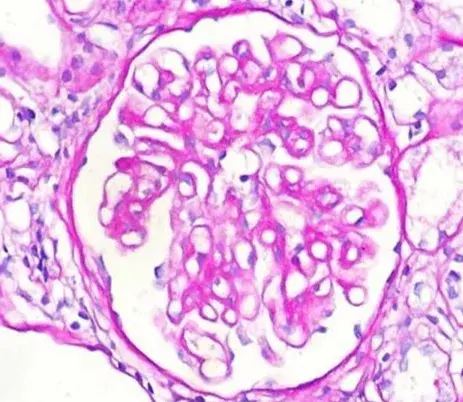

Nefropatía Membranosa: ¿Y si el paciente no responde al tratamiento inicial?

Nefropatía Membranosa: ¿Y si el paciente no responde al tratamiento inicial?

Cómo tratar la Nefropatía Membranosa de manera práctica

Cómo tratar la Nefropatía Membranosa de manera práctica